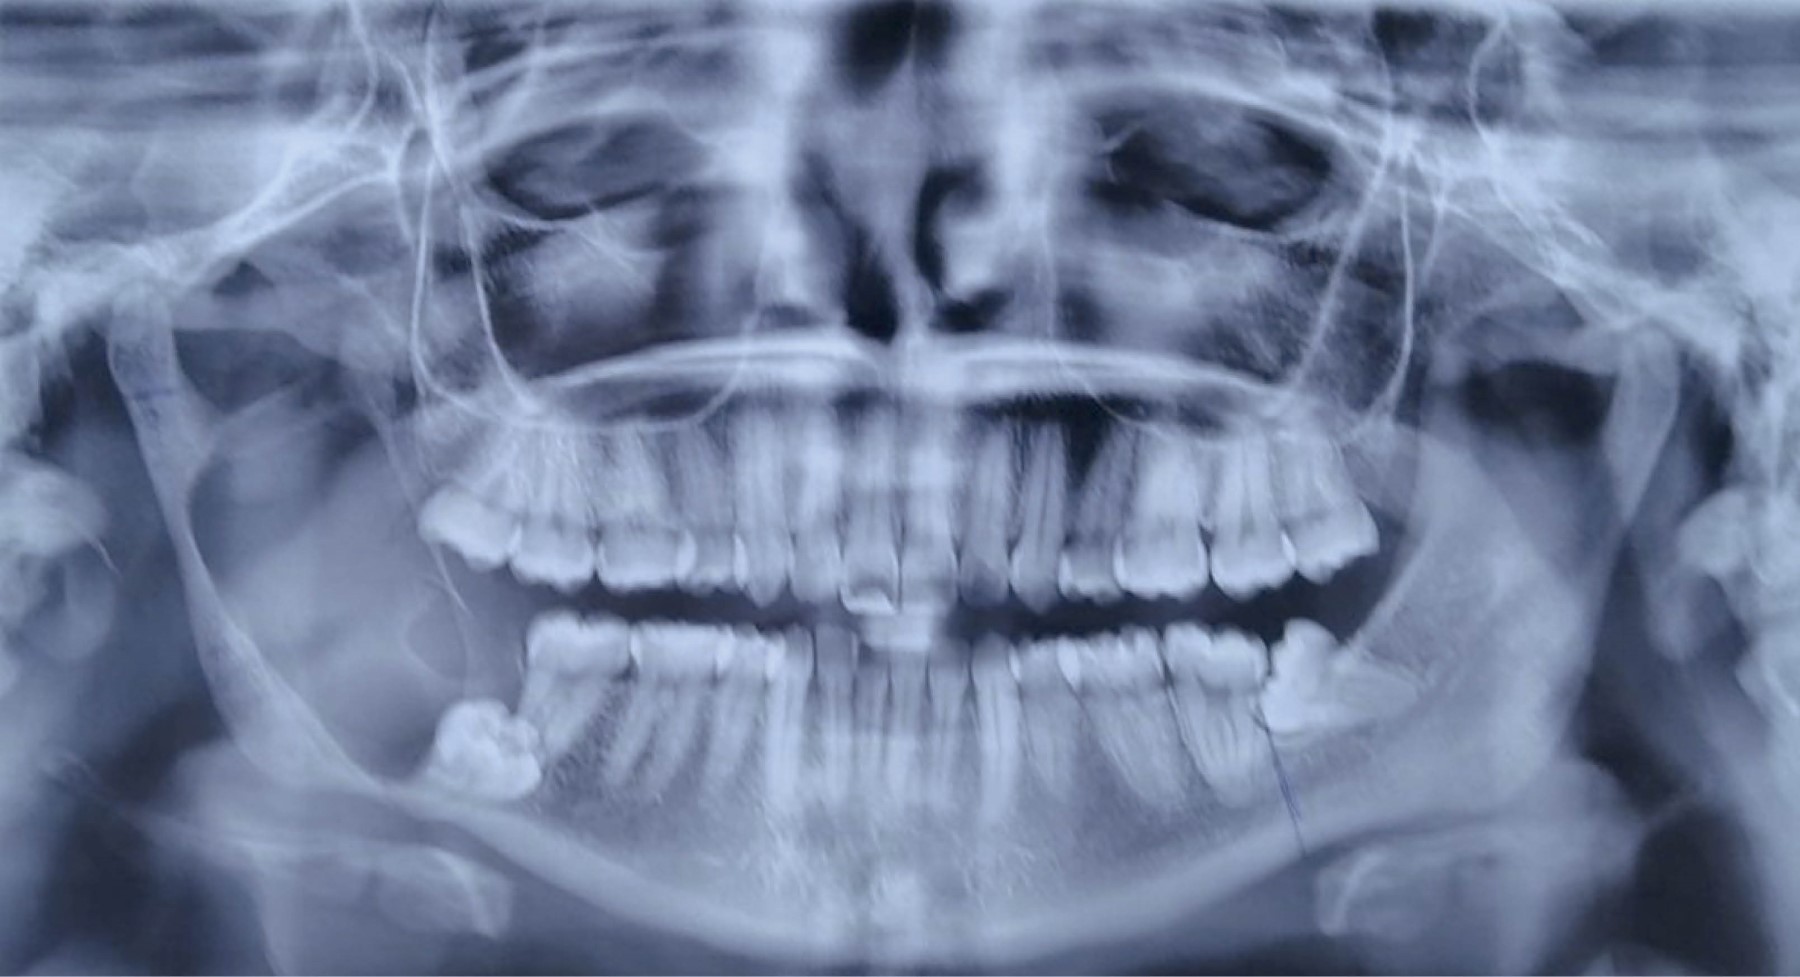

Mujer de 25 años, sin patologías crónicas ni antecedentes traumáticos previos, enviada a nuestro servicio posterior a sufrir caída de su propio plano de sustentación, con trauma dental sin pérdida de piezas dentarias que se manifestó con dolor local. Durante su protocolo de estudio se solicitó una ortopantomografía (Figura 1), observando una lesión quística en cuerpo mandibular derecho. Fue valorada por cirujano maxilofacial, quien realizó una biopsia de la lesión, con resultado de ameloblastoma uniquístico. A la exploración física se encontró asimetría facial a expensas de aumento de tamaño mandibular derecho (Figura 2), el cual no había sido percibido por la paciente. Se hizo la planeación prequirúrgica mediante tomografía de macizo facial y pierna derecha, con reconstrucción ósea, así como impresión de moldes anatómicos tridimensionales y la planeación de las osteotomías (Figura 3). El procedimiento se realizó previo marcaje convencional de pierna derecha; se tomó el peroné respetando 7 cm proximales y distales, con una isla cutánea de 2 × 5 cm. Al mismo tiempo se realizó la resección del tumor, disecando el cuerpo mandibular derecho y la rama ascendente hasta el cuello condilar ipsilateral, así como preparación de la arteria y vena facial derecha. Se procedió a la anastomosis término-terminal con prolene 9-0 con la arteria y vena facial. Posteriormente se realizaron las osteotomías según las guías de corte. Se fijó el colgajo de peroné en su zona receptora con una placa anatómica 2.0 previamente doblada. Se tomaron estudios de imagen en el postoperatorio, así como un seguimiento fotográfico en su evolución durante seis meses después de su cirugía, en la cual observamos una adecuada evolución clínica y radiológica, sin complicaciones postoperatorias y con una simetría facial satisfactoria (Figuras 4 y 5).

Figura 1